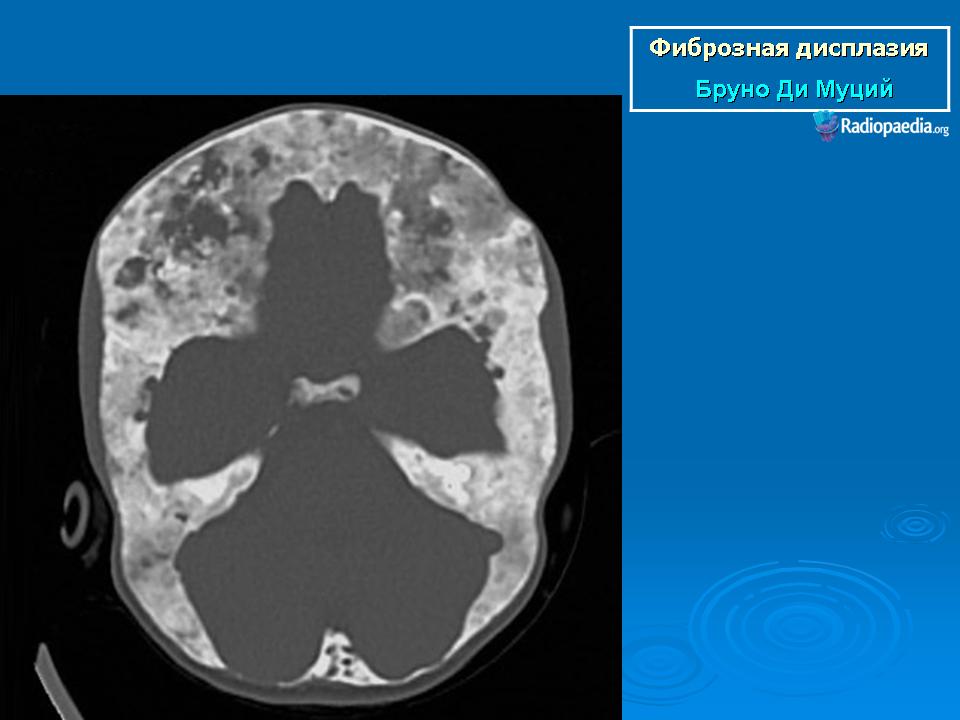

Локализация: для монооссальной фиброзной дисплазии характерно поражение одной из костей лицевого черепа, а также бедренной или большеберцовой кости, реже одного ребра; при полиоссальной фиброзной дисплазии страдают в первую очередь бедренная, большеберцовая и тазовые кости, не исключено и поражение мелких костей стопы, черепа, реже ребер. Рентгенологическая картина фиброзной дисплазии разнообразна. Патологические участки могут быть то более плотными, то более прозрачными по сравнению с окружающей костью, иногда имеют вид «матового стекла». Одни очаги четко отграничены зоной склероза, контуры других расплывчатые, что особенно характерно для костей черепа. Нередко выявляются узуры в кортикальном слое, а при наличии перелома — отчетливая периостальная реакция. При макроскопическом исследовании определяются беловато-красные опухолевые очаги разной плотности, в зависимости от степени выраженности их минерализации. Имеются многочисленные кисты, заполненные желтоватой или красноватой жидкостью, и полупрозрачные участки хряща до 3 см в диаметре.

Для фиброзной остеодисплазии, или болезни Брайцева-Лихтенштейна, характерно нарушение костеобразующей функции мезенхимы, проявляющееся в одной или нескольких костях, что ведет к их деформации и образованию в них очагов разрежения, обычно отграниченных от здоровой ткани кости склеротической каймой. Объем пораженной кости при этом может быть увеличен. Чаще поражаются трубчатые кости, но характерные изменения могут отмечаться и в костях черепа. В таких случаях возможны облитерация придаточных полостей носа, деформация глазниц, сужение отверстий в основании мозгового черепа и в лицевом черепе, ведущее к нарушению функции проходящих через них нервов и сосудов. Заболевание, возможно, наследственное, проявляется с детских лет. Описал в I927 г. отечественный хирург В.Р. Брайцев (1878-1964), несколько позже - американский патологоанатом L. Lichtenstein (1906-1977).